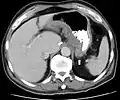

صورة طبقية تظهر مرض كرون في قاع المعدة

صور الأمعاء الدقيقة الإشعاعية قد تساعد في تشخيص مرض كرون وتكون مفيدة فقط إذا كان المرض في الأمعاء الدقيقة. تنظير القولون وتنظير المعدة يظهر رؤيا واضحة فقط للجزء الأخير من المعي اللفائفية وبداية الإثني عشر لكنها لا تعطي معلومات عن باقي الأمعاء الدقيقة. لذلك يتم استخدام صور باريوم الإشعاعية، حيث يتم حقن المريض ب سلفات الباريوم وأخد الصور الإشعاعية طوال الوقت، المفيدة للبحث عن الالتهاب وتضيق الأمعاء الدقيقة.[102][103] حقن الباريوم الشرجية، حيث يتم إدخال الباريوم في المستقيم واستعمال جهاز الأشعة لأخذ صور للأمعاء، يستخدم نادرا في فحص مرض كرون بسبب وجود تنظير القولون الذي يغني عن ذلك. ولكنهم يفيدوا للتعرف على التشوهات التشريحية عندما يحدث تضيق للقولون بحيث لا يمكن لجهاز التنظير أن يدخل، أو في اكتشاف الناسور القولوني( في هذه الحالة تكون المادة المستخدمة هي المواد المعالجة باليود).[104] الصورة الطبقية والتصوير بالرنين المغناطيسي مهمات لتحديد إصابة الأمعاء الدقيقة من خلال استخدام برتوكولات الحقن المعوي.[105] ويتم استخدامهم أيضا لفحص المضاعفات الباطنية الناتجة عن مرض كرون، مثل الخراج، انسداد الأمعاء الدقيقة، أو الناسور.[106] التصوير بالرنين المغناطيسي خيار آخر لتصوير الأمعاء الدقيقة بالإضافة إلى فحص المضاعفات، مع أنه غالي الكلفة ومتواجد بصورة أقل.[107]